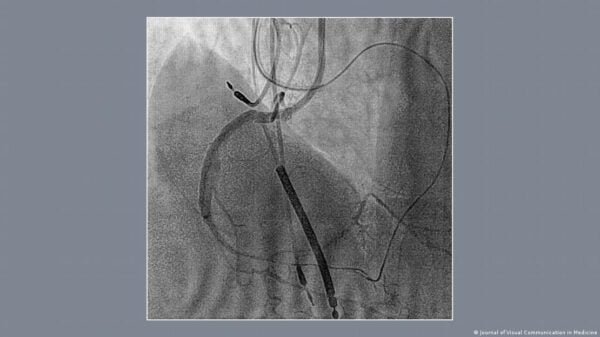

El corazón, ese ícono universal del amor y las emociones, es un símbolo que todos reconocemos instintivamente. Aunque su forma estilizada poco tiene que ver con el órgano que late dentro de nuestro pecho (al parecer), su representación ha estado impresa en nuestra cultura desde tiempos inmemoriales. ¿Pero de dónde proviene esta forma tan característica? Aunque muchos podrían pensar que el símbolo del corazón es una mera abstracción artística, estudios sugieren lo contrario, pues haber una fascinante conexión anatómica detrás de esta representación. Sin embargo, antes de entrar en detalles, el informativo alemán DW Español hizo un breve repaso de su historia. TEORÍAS SOBRE SU ORIGEN Desde la antigua Grecia, filósofos como Aristóteles relacionaron el corazón con las emociones y el amor. Poetas y escritores de la época, como la célebre Safo, también se hicieron eco de esta asociación en sus obras. Sin embargo, según el neurocirujano y escritor holandés Pierre Vinken, la representación gráfica del corazón tal y como la conocemos hoy, que se popularizó en Europa durante el siglo XVI, parece haber surgido en el siglo XIII, quizá inspirada en las descripciones aristotélicas del órgano. Otras teorías sugieren que el clásico logotipo del corazón representa la hoja de una especie extinta de hinojo gigante llamada silfio, utilizada en la antigua Grecia y Roma como condimento, medicina y anticonceptivo. También se especula que podría derivar de formas anatómicas como los senos o las nalgas, o incluso de la hoja de nenúfar o la hiedra. TEORÍA ALTERNATIVA No obstante, un estudio reciente publicado en el Journal of Visual Communication in Medicine propone una teoría alternativa, más relacionada con observaciones anatómicas precisas realizadas en la antigüedad. Gracias a la angiografía coronaria, técnica moderna que emplea un tinte especial y rayos X para observar las arterias del corazón, los científicos han descubierto que la inyección simultánea de contraste en las arterias coronarias produce una imagen sorprendentemente similar al símbolo del corazón. Esto sugiere que la silueta del corazón podría tener un origen anatómico preciso. Este hallazgo plantea la intrigante posibilidad de que los antiguos anatomistas hayan vislumbrado este patrón mucho antes de que la ciencia moderna lo revelara. HIPÓTESIS PLAUSIBLE Los autores del estudio se preguntan si los estudios anatómicos realizados desde la época de Galeno hasta Vesalio, junto con artistas como Leonardo da Vinci y Miguel Ángel, que realizaron autopsias para mejorar su comprensión de la anatomía humana, pudieron influir en la creación del símbolo del corazón. Es posible que, utilizando técnicas rudimentarias de moldeo de la circulación coronaria, estos primeros estudiosos hayan observado una forma similar a la que hoy reconocemos. Aunque esta teoría sigue siendo de naturaleza conjetural y se necesitan más estudios históricos para confirmarla, los autores del nuevo estudio sugieren que puede ser “la hipótesis más plausible para explicar la correspondencia exacta de nuestras imágenes con la antigua imagen arquetípica del corazón”. (Fotos: Tomadas de DW Español) Compartir Navegación de entradas León, municipio de Guanajuato con más casillas especiales Transcurre sin incidentes mayores la votación en Guanajuato